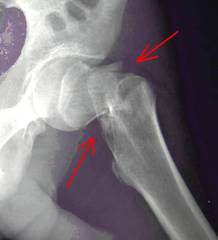

Anziani di Trani, cautelatevi: se vi fratturaste il femore, l'unico ospedale per operarvi è Canosa

A partire da questo mese, e fino a nuova disposizione, l'unico plesso ospedaliero dell'intera Asl Bt in cui gli anziani dovranno ricoverarsi ed operarsi per fratture al femore e dintorni sarà quello di Canosa di Puglia. Infatti, il direttore generale, Ottavio Narracci, ha informato tutti gli operatori sanitari che, per l’Ortogeriatria, sarà proprio quel presidio l'unico abilitato in tutto il territorio sanitario.

Una decisione che, sicuramente, restituisce il sorriso alla ... (continua ...)